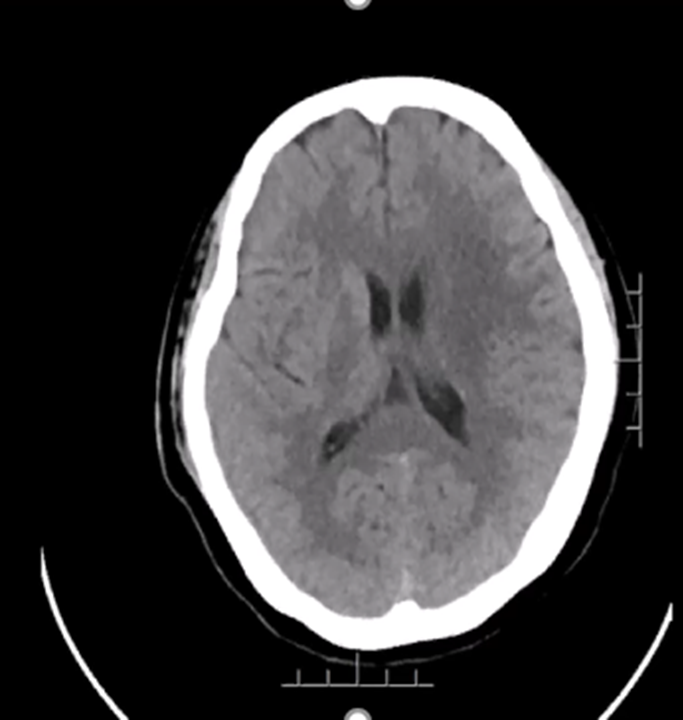

患者:男,76岁,主因"进行性右侧肢体无力伴言语不能10小时余"入院。

患者今晨起4点左右自觉头晕不适,无明显特意表现,未给予重视,并于早6点半左右自行进食,进餐后自觉右侧肢体活动不佳,并摔倒于家中,被家属发现后打120送至我院急诊,救护车中,患者病情出现好转,上肢抬举及下肢负重均改善,查头颅CT考虑新发脑梗死,给予办理入院手续,午1130患者家属欲办理住院手续过程中,突发言语不能,同时右侧肢体出现活动不能,病情明显加重;

给予安排脑血管造影评估颅脑情况;做术前准备。

既往史:血糖波动病史1年余,平素空腹血糖7mmol/L,未系统就诊治疗。10余年前曾就诊考虑心绞痛,平素间断应用拜阿司匹林、硝酸甘油;

查体:嗜睡状态,完全运动性失语,双眼左侧凝视,左侧肢体可见自主活动,肌力约4+级,右侧肢体未见自主活动,肌力约0级。

影像诊断

DSA

结论:左侧颈动脉起始部位出现断流,右侧颈动脉没有明显代偿,血管形态较光滑。